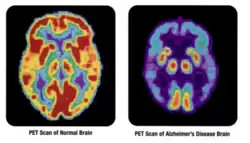

Ядерная медицина применяется в следующих областях (на примере США): кардиология — 46 % от общего числа диагностических исследований, онкология — 34 %, неврология — 10 %[4]. В частности, в онкологии (радиобиология опухолей) ядерная медицина выполняет такие задачи, как выявление опухолей, метастазов и рецидивов, определение степени распространённости опухолевого процесса, дифференциальная диагностика, лечение опухолевых образований и оценка эффективности противоопухолевой терапии[5].